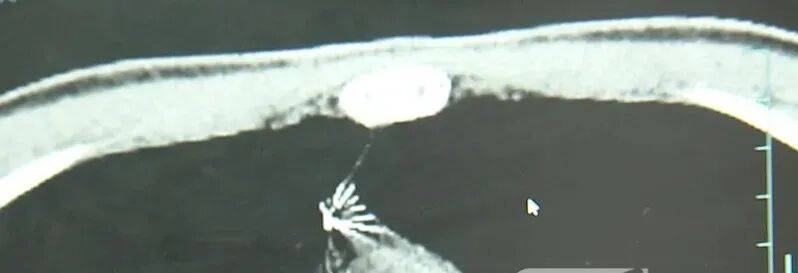

进一步的CT检查确认,异物是一枚金属针,斜插在肺组织内,位置十分凶险。

杭州市第一人民医院心胸外科副主任冯兴说:“我们看到这个针的尖锐部,正好指向他体内的一个大血管,边上是上腔静脉和胸主动脉,因此这个针稍有不慎,就有可能造成周边血管的损伤,甚至危及生命。”

医生推测,那枚针很可能就是在那时候扎入体内的。针在小陆体内滞留了十几年,既没有引发感染,也没有造成气胸,堪称医学奇迹。上周四,医院为小陆实施了mini单孔胸腔镜微创手术,切口仅两厘米左右,成功将针完整取出。